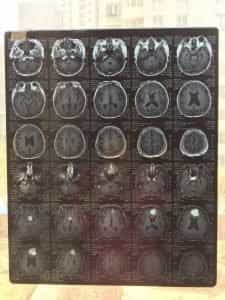

السيد لوان صحفي وكاتب، والكتابة والقراءة هما أهم ما في حياته. لسوء الحظ، قبل عام، فقد السيد لوان بصره فجأة في عينه اليسرى، وتدهور بصره في عينه اليمنى بسرعة. أظهرت صورة الرنين المغناطيسي للدماغ في المستشفى المحلي وجود ورمين سحائيين، أحدهما في المنجل المخي والآخر في منطقة السرج. على الرغم من أن الورم السحائي ورم حميد، إلا أنه تسبب في ضغط شديد على العصب البصري، مما استدعى استئصاله. مع ذلك، فإن المخاطر الجراحية مرتفعة للغاية نظرًا لسنه، بالإضافة إلى معاناته من ارتفاع ضغط الدم لمدة 15 عامًا. لذلك، اقترح المستشفى المحلي العلاج التحفظي.

من خلال التصوير بالرنين المغناطيسي قبل وبعد الجراحة، يمكننا أن نرى أن الورم قد تمت إزالته بالكامل بعد الجراحة.